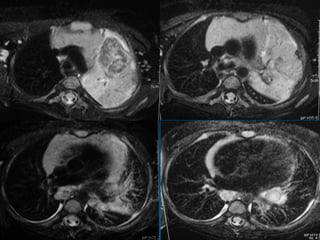

• #3 Συστηματική προσέγγιση